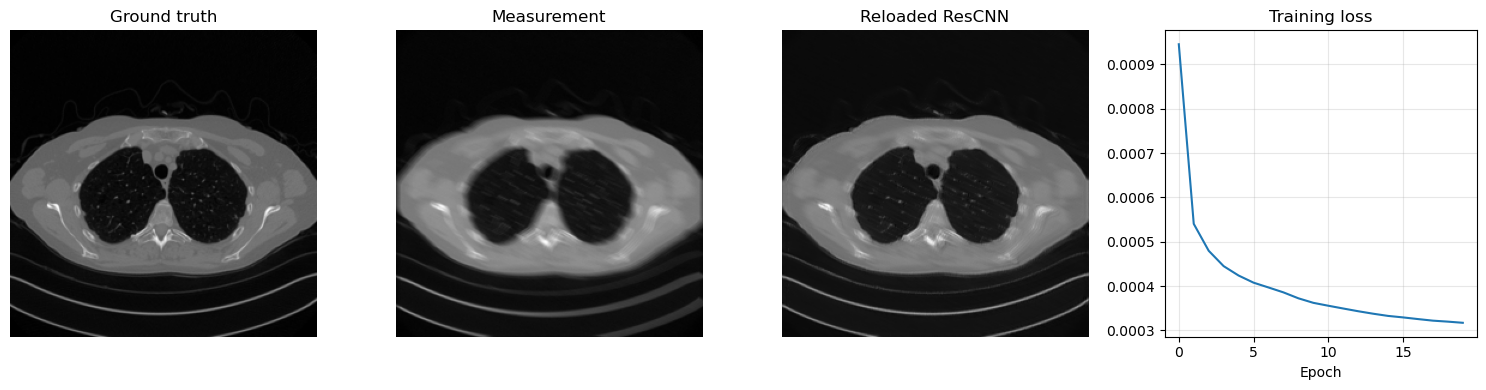

Training a residual model follows exactly the same logic as for the plain CNN, but now the network learns a correction to be added back to the corrupted input. The code below trains a ResCNN for 50 epochs on the Mayo motion-blur task, saves the learned parameters in ../weights/ResCNN.pth, reloads them, and visualizes one reconstruction together with the loss history.

plt.figure(figsize=(15, 4))

plt.subplot(1, 4, 1)

plt.imshow(x_true.cpu().squeeze(), cmap='gray')

plt.title('Ground truth')

plt.axis('off')

plt.subplot(1, 4, 2)

plt.imshow(y_delta.cpu().squeeze(), cmap='gray')

plt.title('Measurement')

plt.subplot(1, 4, 3)

plt.imshow(x_rec.cpu().squeeze(), cmap='gray')

plt.title('Reloaded ResCNN')

plt.subplot(1, 4, 4)

plt.plot(history)

plt.title('Training loss')

plt.xlabel('Epoch')

plt.grid(alpha=0.3)

plt.tight_layout()

plt.show()

Epoch 1/20: 100%|██████████| 414/414 [03:03<00:00,  2.26it/s, avg_loss=0.000945, batch_loss=0.000529]

Epoch 2/20: 100%|██████████| 414/414 [02:58<00:00,  2.32it/s, avg_loss=0.000540, batch_loss=0.000480]

Epoch 3/20: 100%|██████████| 414/414 [02:59<00:00,  2.30it/s, avg_loss=0.000480, batch_loss=0.000528]

Epoch 4/20: 100%|██████████| 414/414 [03:00<00:00,  2.30it/s, avg_loss=0.000445, batch_loss=0.000473]

Epoch 5/20: 100%|██████████| 414/414 [02:59<00:00,  2.31it/s, avg_loss=0.000424, batch_loss=0.000369]

Epoch 6/20: 100%|██████████| 414/414 [02:55<00:00,  2.35it/s, avg_loss=0.000408, batch_loss=0.000295]

Epoch 7/20: 100%|██████████| 414/414 [03:02<00:00,  2.27it/s, avg_loss=0.000397, batch_loss=0.000360]

Epoch 8/20: 100%|██████████| 414/414 [03:11<00:00,  2.16it/s, avg_loss=0.000386, batch_loss=0.000393]

Epoch 9/20: 100%|██████████| 414/414 [03:05<00:00,  2.23it/s, avg_loss=0.000372, batch_loss=0.000459]

Epoch 10/20: 100%|██████████| 414/414 [03:06<00:00,  2.22it/s, avg_loss=0.000362, batch_loss=0.000244]

Epoch 11/20: 100%|██████████| 414/414 [03:06<00:00,  2.22it/s, avg_loss=0.000356, batch_loss=0.000393]

Epoch 12/20: 100%|██████████| 414/414 [03:05<00:00,  2.23it/s, avg_loss=0.000349, batch_loss=0.000293]

Epoch 13/20: 100%|██████████| 414/414 [03:07<00:00,  2.21it/s, avg_loss=0.000343, batch_loss=0.000334]

Epoch 14/20: 100%|██████████| 414/414 [03:08<00:00,  2.20it/s, avg_loss=0.000338, batch_loss=0.000355]

Epoch 15/20: 100%|██████████| 414/414 [03:06<00:00,  2.22it/s, avg_loss=0.000333, batch_loss=0.000342]

Epoch 16/20: 100%|██████████| 414/414 [03:17<00:00,  2.10it/s, avg_loss=0.000329, batch_loss=0.000335]

Epoch 17/20: 100%|██████████| 414/414 [03:06<00:00,  2.22it/s, avg_loss=0.000325, batch_loss=0.000250]

Epoch 18/20: 100%|██████████| 414/414 [03:07<00:00,  2.21it/s, avg_loss=0.000322, batch_loss=0.000306]

Epoch 19/20: 100%|██████████| 414/414 [03:10<00:00,  2.17it/s, avg_loss=0.000320, batch_loss=0.000276]

Epoch 20/20: 100%|██████████| 414/414 [03:07<00:00,  2.21it/s, avg_loss=0.000317, batch_loss=0.000319]

Saved ResCNN weights to: C:\Users\tivog\computational-imaging\years\2025-26\weights\ResCNN.pth

../_images/695b71f30c4305098b7c0930b64320c03e5bde502d9dd21275ffc704c9a52354.png